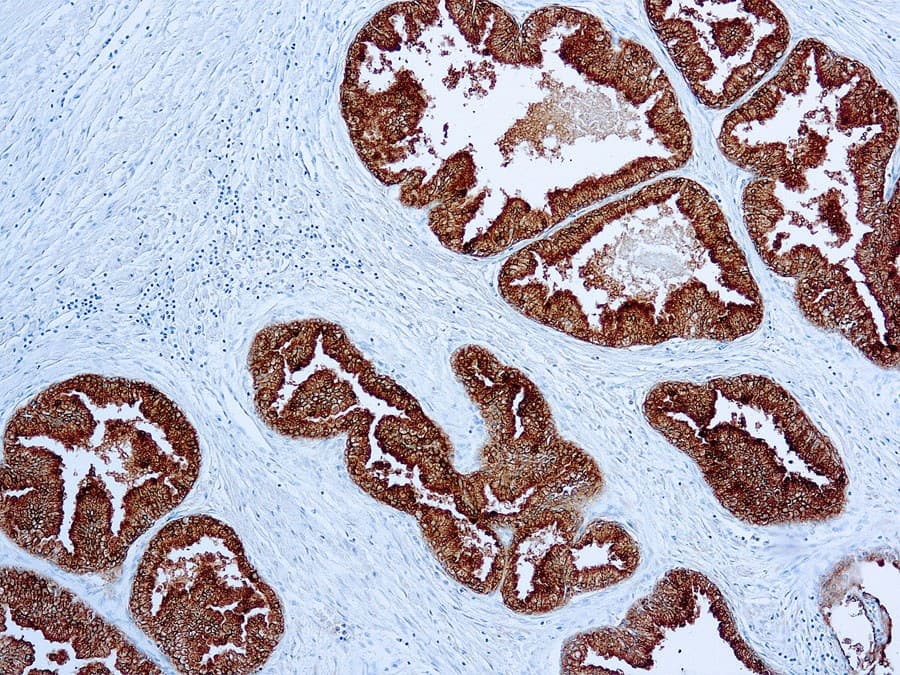

L’immunohistochimie (IHC) anti-PSAP (phosphatase acide prostatique ; PAP ; gène : ACPP) est utilisée comme marqueur d’appoint de la différenciation prostatique en pathologie génito-urinaire (GU). Elle est le plus souvent appliquée dans le contexte des carcinomes métastatiques de primitif inconnu ainsi que dans le diagnostic différentiel entre adénocarcinome prostatique et carcinome urothélial. L’expression de la PSAP est typiquement observée sous forme d’un marquage cytoplasmique dans l’épithélium prostatique bénin et dans de nombreux adénocarcinomes prostatiques conventionnels (acineux).

- Sensibilité pour l’origine prostatique : La PSAP montre une positivité fréquente dans l’adénocarcinome prostatique acineux. La sensibilité rapportée varie selon les études et le type d’échantillon (tumeur primitive versus métastase) et peut être diminuée dans les tumeurs peu différenciées, traitées, ou à petites cellules/neuroendocrines.

- Caractéristiques analytiques : Les anticorps monoclonaux anti-PSAP sont appliqués sur des tissus fixés au formol et inclus en paraffine (FFPE) avec récupération antigénique par chauffage (heat-induced epitope retrieval) et détection par système polymérique, produisant un marquage cytoplasmique de l’épithélium prostatique.